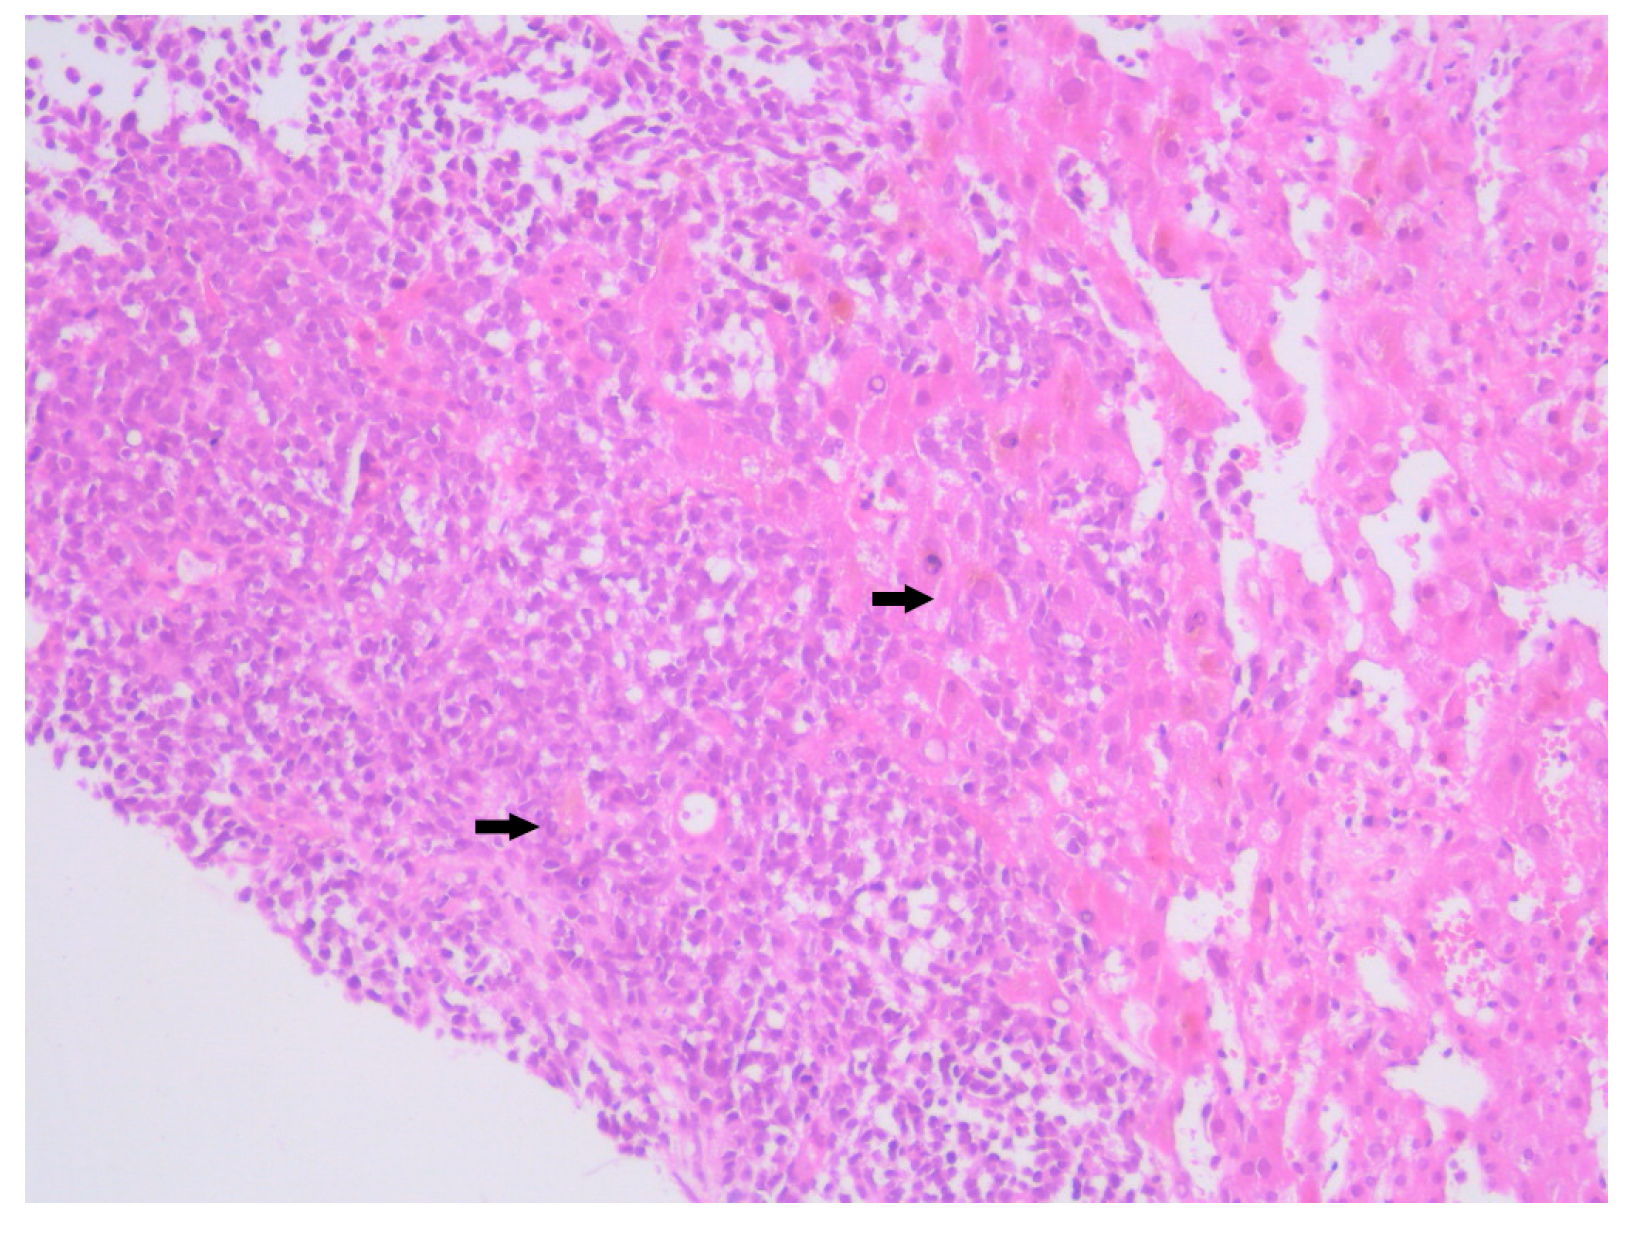

Histopathological examination of the liver biopsy revealed fragments of hepatic parenchyma measuring 10 × 1 mm, with tumoral infiltration by small, round blue cells exhibiting indistinct cytoplasmic borders, scant eosinophilic cytoplasm and round to oval nuclei that were either hyperchromatic or euchromatic, with finely granular chromatin and absent nucleoli. Occasional mitotic figures (4 per 3 HPFs) were identified. The morphology was consistent with a small round blue cell tumor, raising differential diagnostic considerations (Figure 4, Figure 5 and Figure 6). Small round blue cell tumors involving the liver include lymphoma, plasmacytoma, metastatic small-cell lung carcinoma, high-grade neuroendocrine carcinoma, metastatic melanoma, metastatic neuroblastoma and Ewing sarcoma. In contrast to these entities, MCC usually presents with a rapidly growing cutaneous primary tumor, satellite or in-transit metastases and early involvement of regional lymph nodes, as seen in our patient. The combination of morphology (small round blue cells with scant cytoplasm and neuroendocrine features), the presence of a violaceous primary lesion on a sun-exposed site, satellite nodules, marked axillary lymphadenopathy and rapid multiorgan dissemination made MCC the most consistent diagnosis, despite the absence of immunohistochemistry. To clarify the cellular origin and reach a definitive diagnosis, correlation with clinical and paraclinical data, along with immunohistochemical testing (e.g., CK AE1/AE3, CK20, CD56, Chromogranin A, SOX10, CD20, CD3, CD138), would have been essential. The liver biopsy was obtained while the patient was hemodynamically unstable, and within hours he developed biopsy-related hemoperitoneum, shock and multiorgan failure, requiring transfer to the ICU. Due to the rapid clinical deterioration and death shortly afterward, the sample could not be processed for IHC in time, and further invasive tissue sampling was no longer ethically indicated. Nevertheless, the combination of clinical presentation (violaceous cutaneous tumor with satellite nodules), imaging (multiorgan metastases) and morphology of the liver sample (small round blue cells with neuroendocrine features) supported the presumptive diagnosis of metastatic MCC. According to the 8th edition of the American Joint Committee on Cancer (AJCC) staging system for MCC, this case corresponds to Stage IV—cT2N3M1c disease. The T2 classification applies because the primary cutaneous tumor was >2 cm. N3 reflects the presence of clinically evident, macroscopic lymph node involvement together with in-transit metastases (satellite cutaneous nodules). The M1c designation is supported by multiple visceral metastases involving the liver, spleen and suspected bone lesions on CT imaging.

Figure 4. Hematoxylin–Eosin staining, 4× magnification (HE 4×): Biopsied fragment of hepatic parenchyma showing a tumoral proliferation located at one end, occupying approximately three high-power fields (HPFs). Arrows indicate the area of tumoral infiltration at the edge of the hepatic parenchyma.